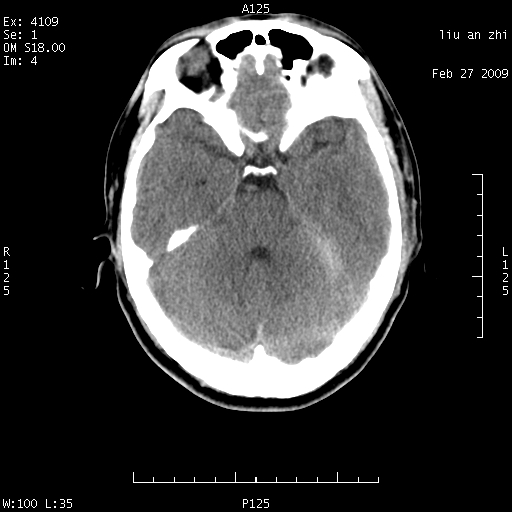

7天后复查头颅ct片:

小脑幕前后7天变化不明显,考虑正常,不考虑sah,7天应该基本吸收了。

ct18448的结果:mri检查左侧天幕下血肿

以下是引用深蓝一号在2009-3-9 16:22:00的发言:[br]ct18448的结果:mri检查左侧天幕下血肿。